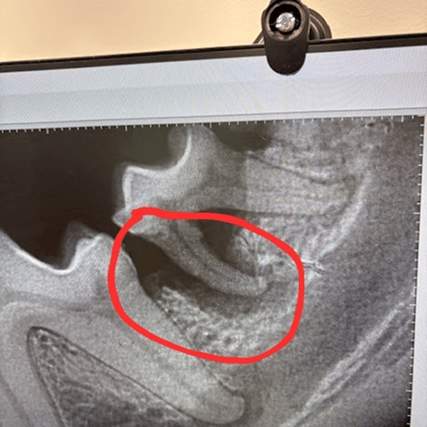

During her dental procedure, our veterinarians discovered severe bone loss around several teeth caused by advanced periodontal disease, a common but often hidden condition in small-breed dogs. To prevent infection and relieve any pain, 14 compromised teeth were removed.